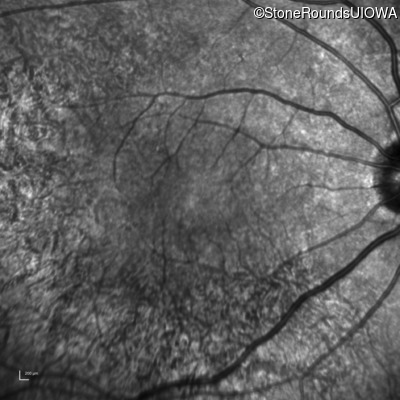

Age at visit: 61 years

OD OS